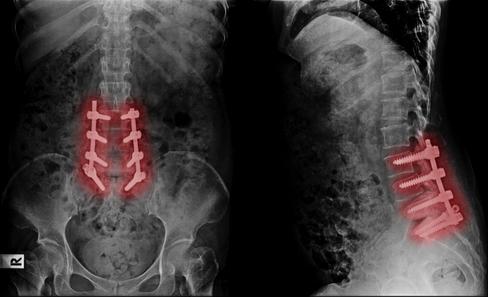

and lengthy recoveries.

Stop missing life’s greatest moments Stop planning life around pain

Back Pain should not mean fusion, screws, and lengthy recoveries Regenerative Medicine is changing how back pain

Back Pain should not mean fusion, screws, and lengthy recoveries Regenerative Medicine is changing how back pain is solved.